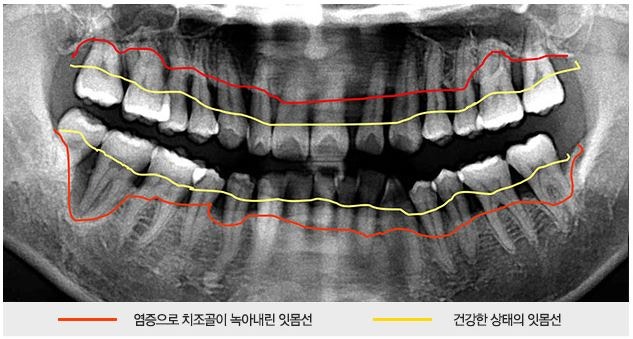

그런데 문제가 되는 것은 환자는 1년에 한 번 하는 스케일링으로도 이가 시린 이유를 제거할 수 있다고 생각하는 부분입니다.보통 치아가 시린다는 것은 잇몸 속에 있는 치석이나 염증이 잇몸을 소실시키고 치아 뿌리 부분이 노출되거나 과도한 힘이나 잘못된 칫솔질 등의 이유로 잇몸부 마모가 생겼다는 것인데 스케일링은 단순히 눈에 보이는 치석을 해결하는 것이기 때문에 시린 치아를 해결하기에는 역부족입니다.